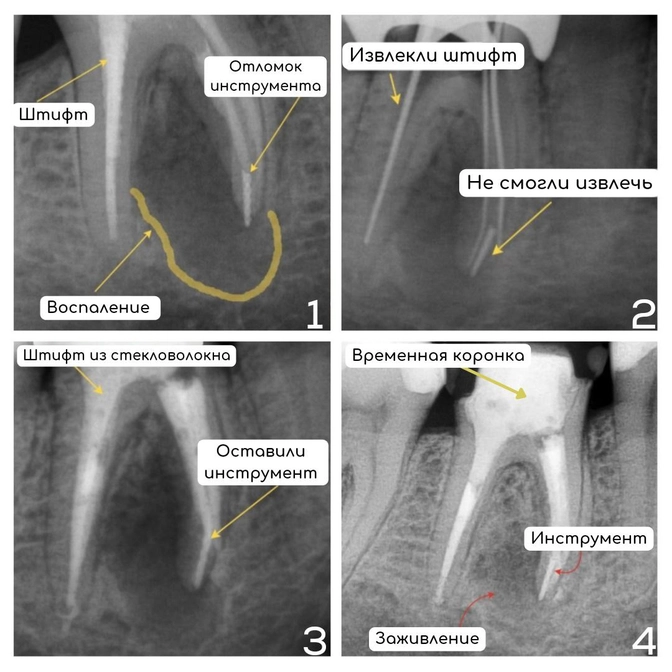

Передечиваем зуб с отломком инструмента в канале

Но под зубом имеется обширное воспаление — это "киста" или апикальный периодонтит.

Плюс ко всему в одном из корней видим отломок инструмента, а в другом корне — штифт.

Всё это нужно было извлечь, прочистить, заложить лекарство и вылечить зуб.

С чем успешно справилась наш эндодонтист Галина Базылева.

✔️Штифт извлекли;

✔️Каналы прочистили и продезинфицировали;

Отломок инструмента достать не удалось — такое бывает.

Но он стерилен и не является причиной "кисты".

✔️Заложили лекарство;

✔️Укрепили зуб стекловолоконным штифтом;

✔️Закрыли временной пломбой.

Заживление контролировали рентгенологически.

Через некоторое время воспаления на снимке уже не было — значит зуб здоров и функционален.

Вы спросите, что с отломком инструмента?

Его не трогаем.

Хоть доктор Базылева и мастер по извлечению инородных тел из корневых каналов, но в этом случае тактика иная.

Оставляем всё как есть — это самое правильное в такой ситуации, это безопасно и прогнозируемо.